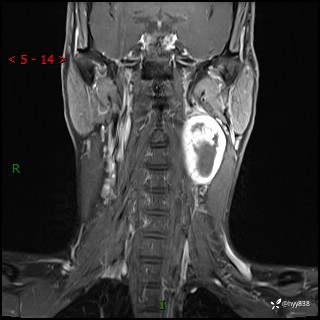

现病史:患者约3年前因感冒发现左侧颈部长一肿物,约半个鸡蛋大小,无明显疼痛及其他不适,一直未行特殊处理。3个月前发现左侧颈部肿物变大,随后至当地市第二人民医院耳鼻喉科行左侧颈部彩超示:左侧颈部囊实混合性包块;喉部MPR示:左侧胸锁乳突肌内前方占位,累及左侧喉旁间隙,建议增强扫描。建议手术治疗。患者考虑。随后至我院肿瘤科就诊,行细胞学穿刺示:考虑血管源性肿瘤可能,建议进一步检查。建议至我院口腔科就诊,行颌面部MRI示:左侧颌下腺后方团状异常信号灶,建议增强。建议手术治疗。为求进一步治疗,门诊以“左侧颈部肿物”收入院。 起病以来,患者神志清、精神良好,饮食睡眠良好,大小便正常,体重未见明显变化。

颈部MRI平扫+增强